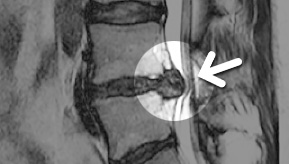

MRI ġ

MRI